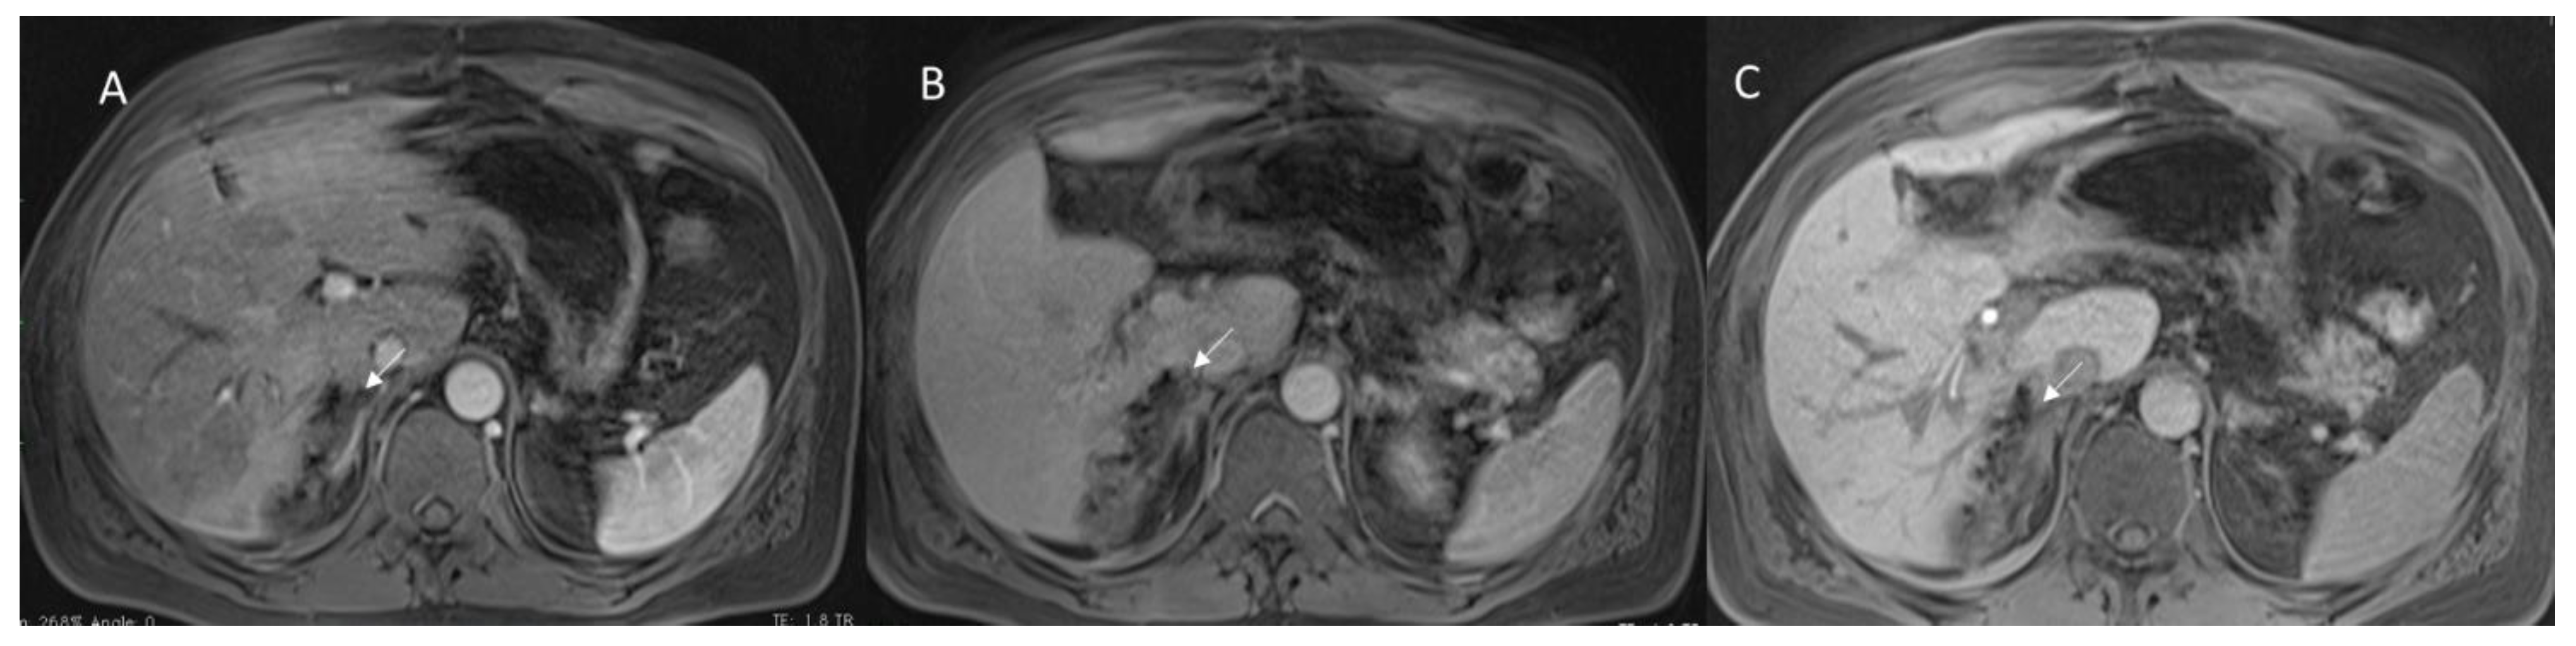

3.1.3. Vascular Thrombosis

3.1.4. Biliary Injuries